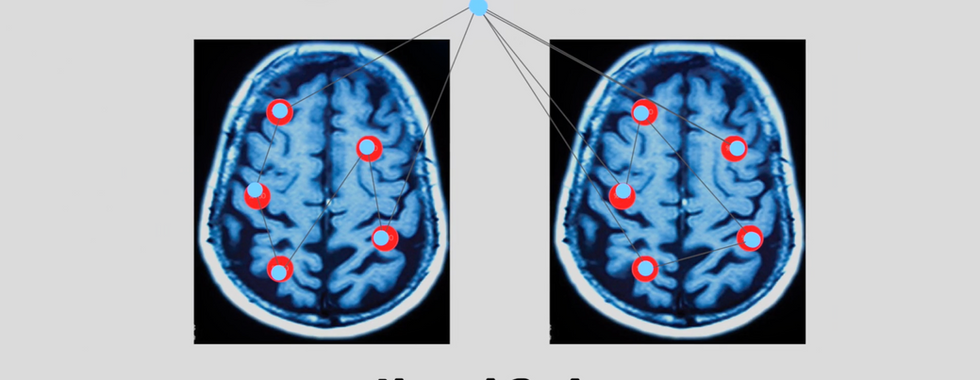

Module 2 (Youth Awareness): Utilized age-appropriate visual metaphors to explain the neurobiological impact of substances on brain plasticity.

Module 3 (Patient Recovery): Targeted the mechanics of the neurological reward system and the cycle of dependency.